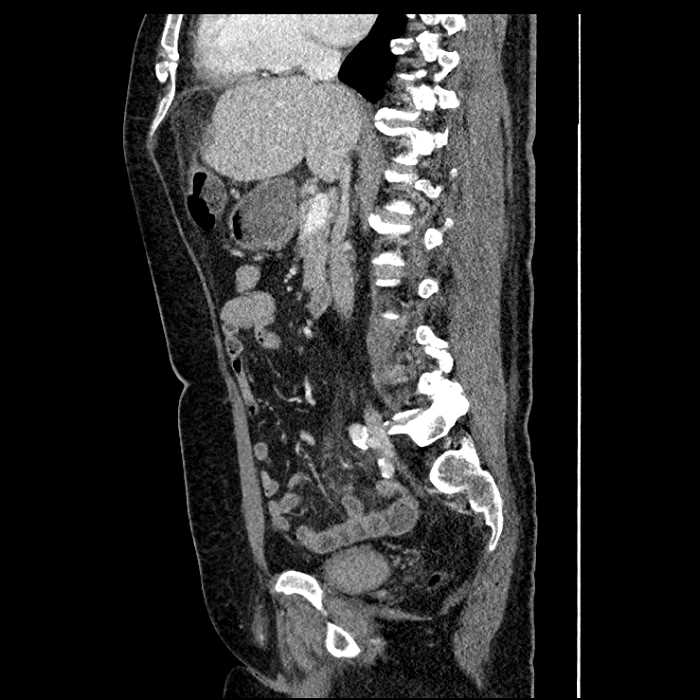

Age: 63

Sex: Male

Indication: Abdominal pain

• Large fluid density structure in hepatic segments 7 and 8 measuring 10 x 7 x 7 cm with internal septation and circumferential ill-defined low density compatible with edema

• Peripherally enhancing subcapsular collections along the anterior margin of the left hepatic lobe measuring 3 x 1 cm and 2 x 1 cm

• Clearly marginated fluid density structure in segment 7 and several other scattered tiny hypodensities, which likely represent cysts

• Mild mural thickening of a segment of the sigmoid colon with adjacent fat stranding and a 1.5 cm fluid and gas collection along the tip of an inflamed diverticulum

• Loss of the normal fat plane between this collection and adjacent loops of small bowel, which demonstrate mural thickening

Acute sigmoid diverticulitis complicated by a small contained perforation and a large abscess in the right hepatic lobe. Additional small subcapsular abscesses along the anterior margin of the left hepatic lobe.

Additionally, loss of the normal fat plane between the peridiverticular collection and adjacent thickened loops of small bowel raises the potential for an enterocolonic fistula.

• The classic CT imaging appearance is a double target sign with internal low density surrounded by an internal enhancing rim (capsule) and a low density external rim (edema)

Hepatic abscess showing the double target sign with low density internally surrounded by a thin inner enhancing rim (red arrow) and ill-defined outer low density rim (yellow arrow). Blue arrow indicates an internal septation. Red arrows: additional smaller subcapsular abscesses. Red arrow: focal contained perforation associated with diverticulitis.